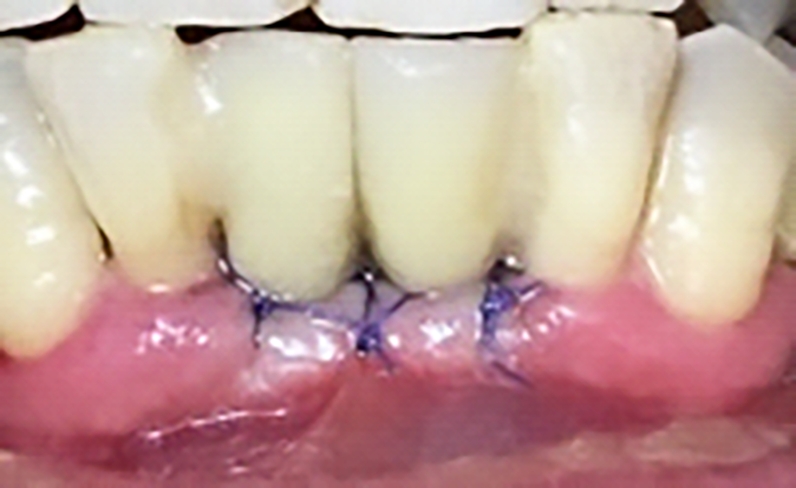

Previa anestesia locale si esegue lo scollamento di un lembo a spessore totale per consentire l’avulsione atraumatica degli elementi 3.1 e 4.1 (figure 1a-1b). Si revisionano le cavità alveolari e si posizionano osso bovino deproteinizzato e una membrana di collagene riassorbibile. Si sutura con filo 5/0, si posiziona un maryland bridge per garantire l’estetica in attesa dell’inserimento implantare e si esegue una radiografia di controllo (figure 2-4).

In seguito all’estrazione degli elementi 3.1 e 4.1 si osserva a una settimana di follow up la perfetta guarigione dei siti (figure 4-5). I successivi follow up mostrano come la rigenerativa abbia ristabilito gli adeguati volumi ossei e grazie all’analisi tridimensionale dei siti implantari è possibile pianificare correttamente il posizionamento degli impianti (figura 6).